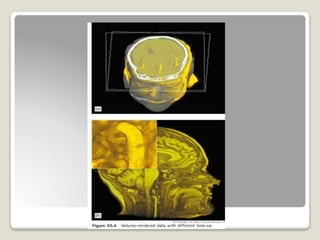

VISUALIZATION OF IMAGE

RENDERING:process of generating images which

represent 3D anatomy with some degree of tissue

transperancy.

VOLUME RENDERING

SURFACE RENDERING

 Triplets of data points

are grouped as the

vertices of adjacent

triangles that

interconnect to make

up entire surface

known as facets.

⚫ Projecting each voxel

on to a viewing plane

with a value related to

the physical property

⚫ Operator may choose

to display only the max

contribution for any

voxel along a ray.

⚫ This produces image

max intensity

projection.(MIP)

⚫ VOLUME RENDERED

images appear diff from

a surface rendered

image in that

anatomical structures

are presented as having

some degree of

transparency.

⚫ Enhances depth

perception

⚫ Increases accuracy

⚫ Placement of surgical

instruments with more

accuracy.